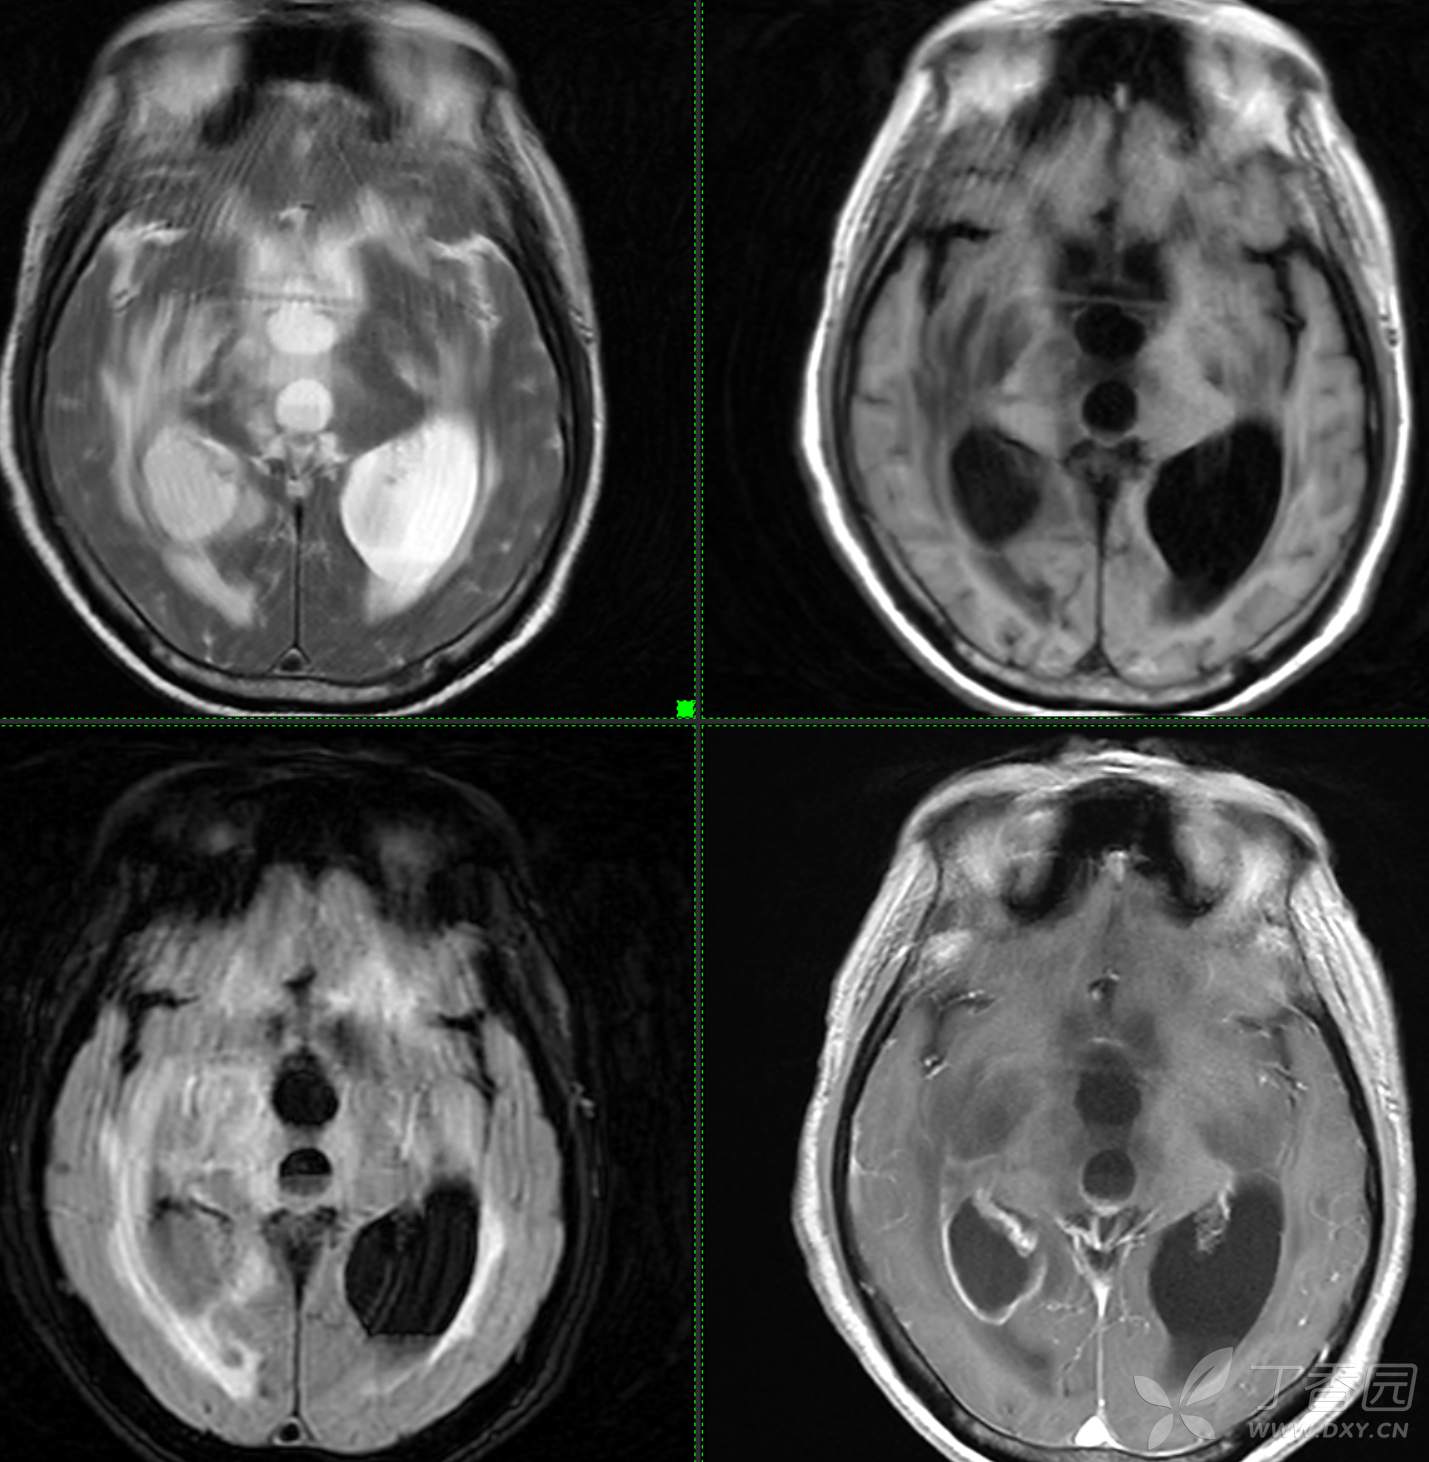

头颈组9:简单分析,诊断不难。

主诉: 【头晕乏力数周,发热1周】

现病史: 患者3周前无明显诱因下出现头晕,无头痛,伴视物模糊,肢体乏力,走路步态不 稳,无意识不清,对答切题,当地医院查血常规示:中性粒细胞分类:77.7%.淋巴细胞分类:15.6%,中性性粒细胞分类:7.1*10^9/L.葡萄糖:22.35mmol/,头颅平扫示:右侧丘脑饱满,密度减低伴低密度灶,占位不排除,两侧半卵圆区、额叶低密度灶,以“1.糖尿病酮症酸中毒,2.颅内占位性病变”收入住院治疗,1周前住院期间出现发热,先后予抗感染,控制血糖等对症支持治疗,2天前无明显诱因下再次出现发热,伴血糖升高,自测体温40℃,血糖20mmol儿,伴气促无胸闷,袖志模糊,反应迟钝,无畏寒寒战,无腹痛腹泻等不适,昨日送至我院就诊